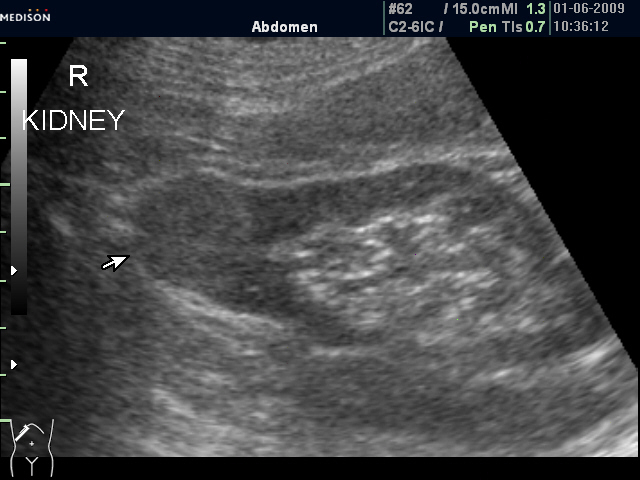

Женщина 72 лет. При УЗИ выявлены два аваскулярные образования: в нижнем полюсе правой почки и у верхнего полюса почки.

Уникальность случая в том, что эти изменения - БЕЗ ДИНАМИКИ с 2005 года.

Опухоль почки?

Без допплера явно опухоль почки